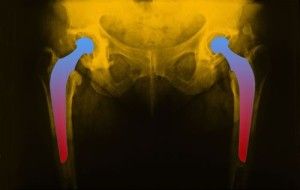

hip-implant-lawsuitA Texas couple file a hip implant lawsuit against DePuy Orthopaedics and parent company Johnson & Johnson for allegedly failing to warn that the Pinnacle hip implant device was dangerous and unsafe for its intended use.

The plaintiffs allege that while most hip replacements use a polyethylene plastic acetabular liner, DePuy’s Pinnacle is a metal-on-metal hip implant. Over time, the Pinnacle implant forces metal to rub against metal which can lead to serious hip implant side effects including metal poisoning of the bloodstream.